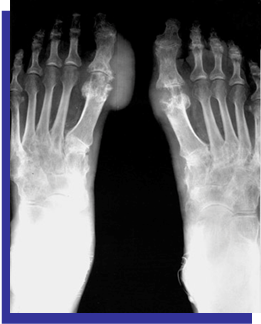

Foot (Figure 3)

Figure 3 Swelling, redness & tenderness of right and left big toes. Big tophi in the right foot.